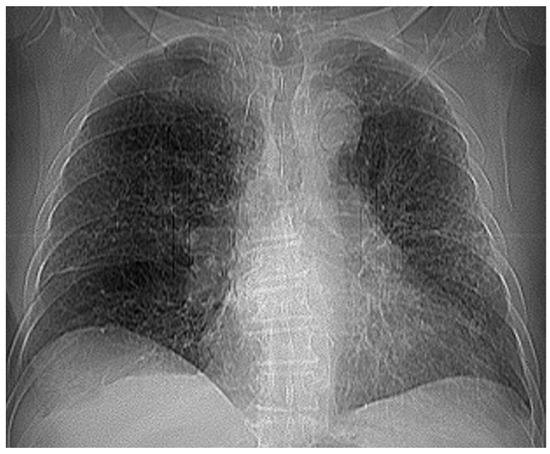

Figure 12 and Figure 13 show the selection of lung portion of interest for patient 3 (VU) and the same image in “Invert color” format.

Figure 14 and Figure 15 present the defined masks for the left lung and right lung, framed in blue borders.

Table 3 shows the known fractal indicators, such as the fractal dimension of the CT image of the left lung, d1L = 1.8836 ± 0.3148m, and the lacunarity, Λ = 0.0279; and the fractal dimension of the right lung, d1R = 1.8772 ± 0.3204, and the lacunarity, Λ = 0.0291.

Figure 12. Selecting the portion of interest of the lungs of patient VU.

Figure 14. Defining the mask for the left lung of the third patient.

Fractalfract 07 00285 g014

Figure 15. Defining the mask for the right lung of the third patient.

Fractalfract 07 00285 g015